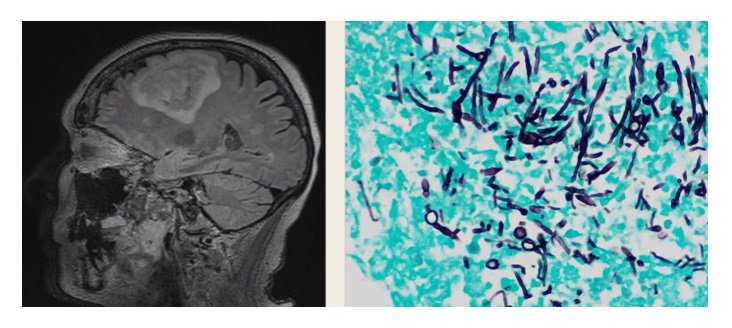

CC: confusion x 3 mo. No F/C. PE: left sided neglect, facial droop, anisocoria

CT (photo). Surgery: cavity with pus and swelling. Path (photo). Culture: growth in 24h

Case diagnosis:

#Scedosporiosis

Culture: #Lomentospora prolificans

BDG+/GM- makes Mucor/Aspergillus less likely

Path: hyphae makes Coccidiodes less likely

1. S. apiospermum, Lomentospora prolificans

2. Environment; inhalation or inoculation

3. Localized (trauma, keratitis) vs. invasive, disseminated (ICH)

4. Dx: culture, path, BDG+/GM-

5. Rx: voriconazole (check MDR profile); combo Rx